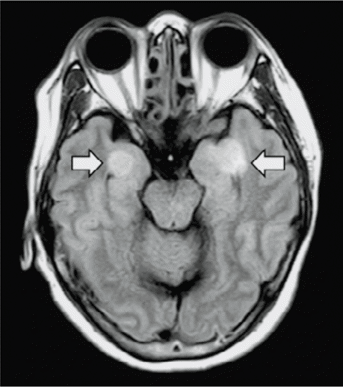

Febbre e tosse non sono i soli sintomi precoci da Coronavirus: quelli neurologici sembrerebbero davvero importanti per una diagnosi tempestiva

9 aprile 2020 - Il Covid-19 spaventa l’intero mondo e i ricercatori lo studiano senza sosta nel tentativo di trovare una cura adeguata. Moltissime infezioni virali possono danneggiare gravemente la struttura e la funzionalità del sistema nervoso causando patologie come encefalite centrale, encefalopatia tossica e gravi lesioni demielinizzanti. Con l'attuale pandemia Covid-19, risulta quindi molto importante sensibilizzare i medici a considerare l'impatto che Covid-19 potrebbe avere sul sistema nervoso centrale. Nella ricerca che troviamo al link sottostante è riportato che oltre ai sintomi sistemici e respiratori, il 36,4 per cento dei pazienti con Covid-19 sviluppa sintomi neurologici precoci come mal di testa, disturbi di coscienza e parestesia. Il lavoro citato conclude quindi ipotizzando che i pazienti con infezioni da Covid-19 devono essere valutati per la possibile presenza di sintomi neurologici. Un’analisi tempestiva del liquido cerebrospinale e la consapevolezza e la gestione delle complicanze neurologiche correlate all'infezione potrebbero quindi risultare fondamentali per migliorare la prognosi dei pazienti critici.